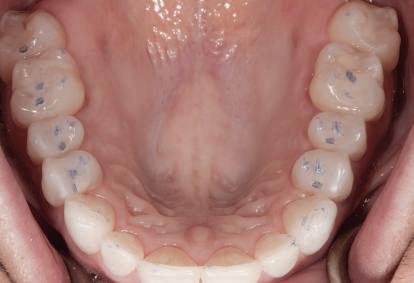

Dacă însă implanturile sunt plasate prea vestibular sau prea superficial, componentele nu permit un design adecvat al bontului, pentru că plasarea marginii este limitată iar conturul facial şi proximal poate fi compromis (fig. 1, 2).

Figurile 3, 4. Întrucât poziţia implantului era mezială faţă de ideal, bonturile individualizate s-au conceput plate pe profilul mezial, dar au prezentat provocări în privinţa conturării restauratoare. 5. Restaurările implantare de la nivelul 1.2. şi 2.2. susţin o FPD metalo-ceramică cimentată între incisivii laterali.

Figurile 1, 2. Compromisurile conturului vestibular şi proximal sunt evidente. Implantul este la nivel tisular, tehnicianul neputând gestiona plasarea marginii sau a profilului intrasulcular pentru a îmbunătăţi estetica. Dacă se concepea un design tradiţional cu hexagon extern, marginea restauratoare s-ar fi putut plasa foarte aproape de interfaţa bont-implant, cu gestionarea mai bună a spaţiului.

Figurile 11-13. Deşi implantul s-a poziţionat la o profunzime normală în raport cu nivelul osului şi al ţesutului moale (fig. 11), va fi imposibilă crearea unei restaurări cu aceeaşi lungime ca dintele contralateral, din cauza plasării coronare a implantului (fig. 12). Restaurarea provizorie demonstrează discrepanţa lungimii dentare (fig. 13). 14. Un bont individualizat CAD/CAM. 15-16. Restaurare implantară la nivelul 1.1. Sondarea osului interproximal pentru a verifica plasarea adecvată a punctului de contact dinspre creasta proximală a osului, cu scopul de a asigura regenerarea completă a papilei interproximale (Fotografii cu amabilitatea lui Don Jayne, DDS). 17. Sunt evidente dificultăţile asociate unui bont standard pentru restaurarea dinţilor anteriori. Întrucât profilul bontului era insuficient, marginile au fost scurtate cu scopul de a lăsa spaţiu pentru conceperea profilului de emergenţă.